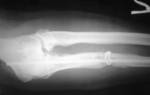

- Серьезные подозрения на дисплазию являются поводом для проведения рентгенографии. Этот метод хоть и считается вредным для детей, но в такой ситуации он не превышает пользы от обследования.

Результаты обследования изучает врач-ортопед, после чего ставит диагноз или опровергает его. При возникающих сомнениях рекомендуется обратиться с описанием УЗИ и снимками с рентгена к другому специалисту, чтобы быть уверенным в достоверности диагноза и назначенном лечении.